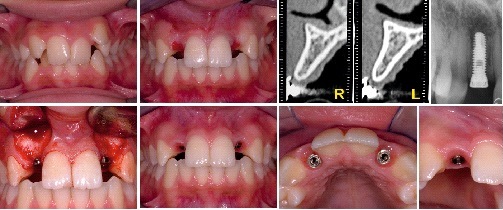

Caso di forte affollamento associato ad agenesia degli incisivi laterali superiori, risolto mediante trattamento ortodontico ed implantologia.

Dettaglio Rx e Corona definitiva in Zirconio

Dettaglio corone Definitive in Zirconio